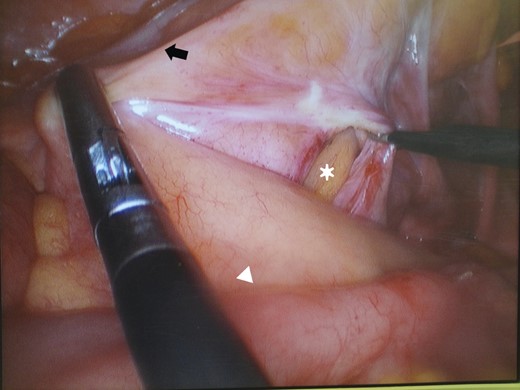

A laparoscopic approach was performed with the patient under general anaesthesia. A 10-mm port for camera was placed umbilicus by an open method. Two other 5-mm ports were placed for instruments in the right upper and lower abdomen. As tracing retrograde from the ileocecal junction, a loop of mid-ileum was incarcerated to ∼2-cm sized defect lateral to the sigmoid colon. First, trying the reduction of small bowel loop by atraumatic grasper gently, detachment of sigmoid lateral attachment was performed. Incarcerated bowel was released as soon as we detached a just little (Fig. 3). Approximately 15 cm of small bowel had been incarcerated in the defect and initially appeared congested but its colour and peristalsis improved rapidly. The hernia defect did not involve the medial aspect of the peritoneum on the sigmoid mesocolon and was confirmed no full-thickness defect. The defect was disappeared and changed to broad space easily from dissection of peritoneal attachment. There was no need to close the defect by intracoporeal suture laboriously. The operation was finished after confirmation of preventing recurrence. The postoperative course was uneventful and the patient was discharged 5 days postoperatively. The patient is free from recurrence.

After reducing the incarcerated ileum (white arrowhead), the defect (asterisk) in the lateral leaf of the sigmoid mesocolon (black arrow) is seen.